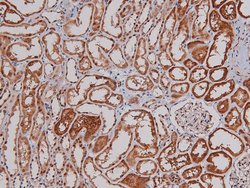

Phospho-p27 Kip1 (Thr157) Polyclonal Antibody for Western Blot, ICC/IF, IHC (P)

| Immunohistochemistry (Paraffin), Western Blot, Immunocytochemistry | |

| A synthesized peptide derived from human CDKN1B(Accession P46527), corresponding to amino acid residues around phosphorylated Thr157. | |